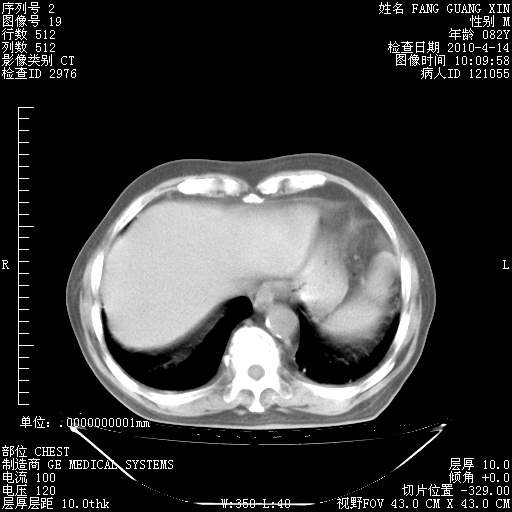

肺部CT平扫未见异常。